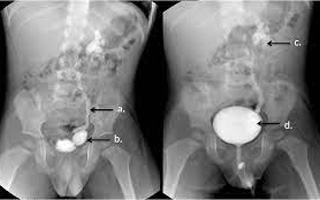

• IVP: An IVP (intravenous pyelogram ) is an imaging test used to look at the kidneys and ureters. The ureters are the narrow tubes that carry urine from the kidneys to the bladder. During the test, the radiologist injects a contrast dye into one of your veins. During an IVP, contrast dye is injected into a vein using an intravenous (IV) line. The dye travels through your bloodstream to your kidneys, which filter it out. The dye collects in the organs of your urinary tract and makes them look bright white on the x-rays.

• MCU: An MCU (Micturating Cysto-Urethrogram)is an x-ray test of the bladder as it fills and empties. It checks to see if the urine is flowing backwards from the bladder up towards the kidneys.